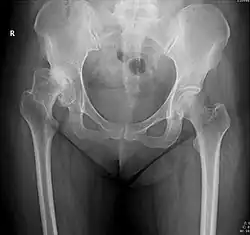

X-ray of hip dysplasia

X-rays of hip dysplasia are one of the two main methods of medical imaging to diagnose hip dysplasia, the other one being medical ultrasonography.[1][2] Ultrasound imaging yields better results defining the anatomy until the cartilage is ossified. When the infant is around 3 months old a clear roentgenographic image can be achieved. Unfortunately the time the joint gives a good x-ray image is also the point at which nonsurgical treatment methods cease to give good results.